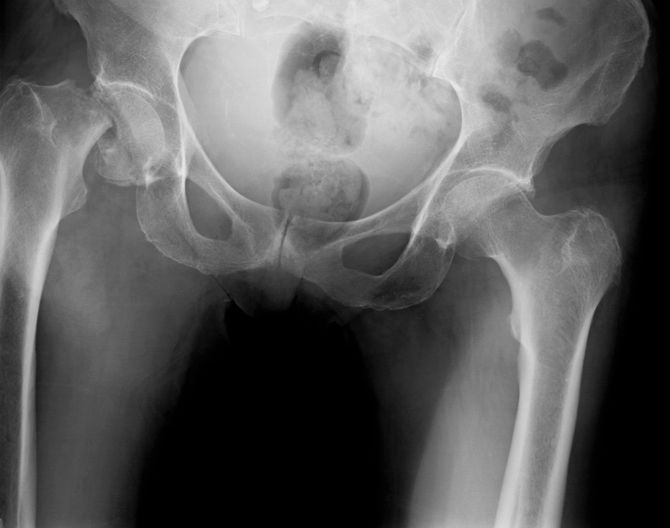

7月。10時ごろ、鈴木さんが夜勤から帰宅すると、母親が自宅で転倒したらしく、動けなくなっていた。父親も自宅にいたが、ただただ困惑し、何もできずにいた。鈴木さんは、母親の足の曲がり具合や左右差からすぐに「大腿骨頚部骨折」を疑い、救急車を要請。コロナ禍だったが、幸いにも近くの病院に搬送され、すぐに手術をしてもらえた。